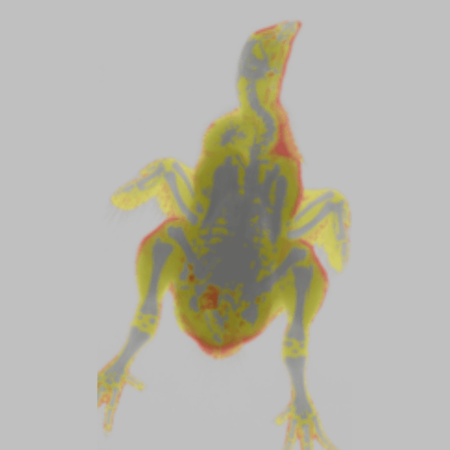

Color Image - Rat

Color Image - Rat. Image Credit: Scintica Instrumentation Inc